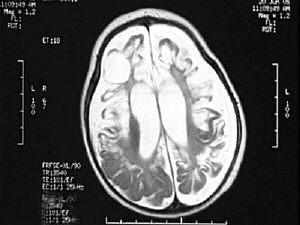

心急如焚的母亲带着娜娜辗转来到了中国人民*海军总医院。儿科主任栾佐看到娜娜的核磁检查结果